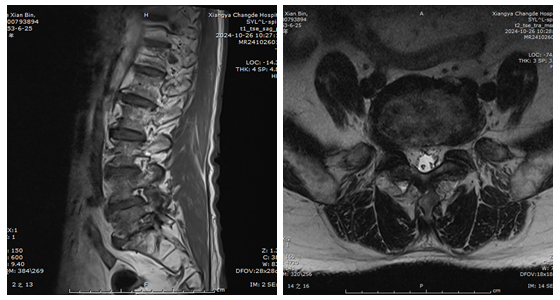

71岁的聂大爷于2月前出现右小腿后外侧放电样疼痛,半月前病情加重,疼痛异常剧烈,导致其整日卧病在床夜不能寐。患者在当地尝试了各种药物治疗,疼痛无缓解,遂前往湘雅常德医院就诊。经过详细的影像学检查,骨科(脊柱外科)团队在陈芳田主任医师的带领下详细评估了患者病情。患者腰椎检查影像学表现为多个腰椎间盘退变,腰5/骶1椎间隙变窄,右侧腰5/骶1极外侧椎间盘突出,椎间孔骨性狭窄。